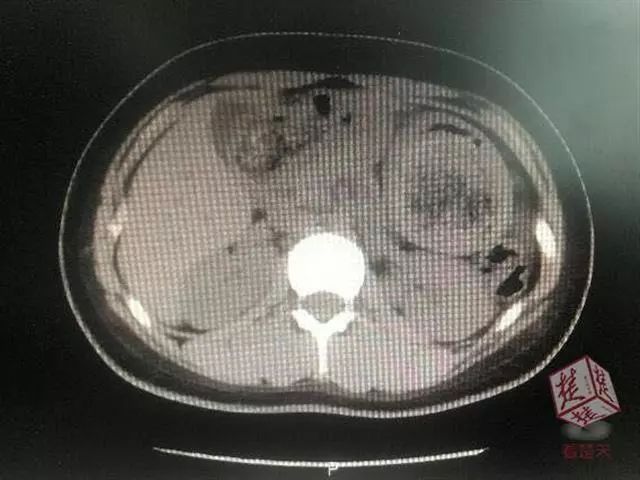

随后,医生给佳佳做腹部CT时,发现她的胃里面有网状的东西,但不知道具体是什么。

胃里的头发缠绕成“硬石头”!

直到做胃镜前,佳佳才告诉妈妈自己一直有吃头发的习惯,果然,医生做胃镜时发现佳佳的胃里全是黑色的头发团!

据佳佳的主刀医生郑教授介绍,佳佳胃里的一根根黑色的头发密密麻麻缠绕成团,跟石头一样硬,在其小肠与大肠交界处也发现了几块稍软的毛发团块,这就是造成她出现肠梗阻的主要原因。